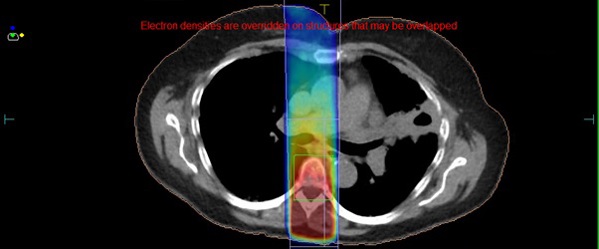

Moving onto the technical news, we have expanded the patient cohorts we treat on the MR-Linac. In May 2022, we treated our first patient with pancreatic cancer. These tumours can be difficult to see with the conebeam CT (CBCT). Using MR imaging we can better visualise target improve treatment accuracy. Using our Adapt to Shape (ATS) online re-planning, the interdisciplinary team can re-contour the position of organs close to the tumour daily and then plan the treatment according to that position.

Below is a picture of a treatment plan for a patient with a pancreas tumour. Note the high dose region in the red colourwash, covering the target (plus a margin for breathing motion) in the blue and cyan lines.